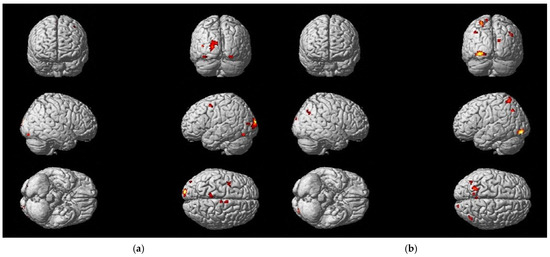

3.3. Differences in Activation Due to Treatment Methods